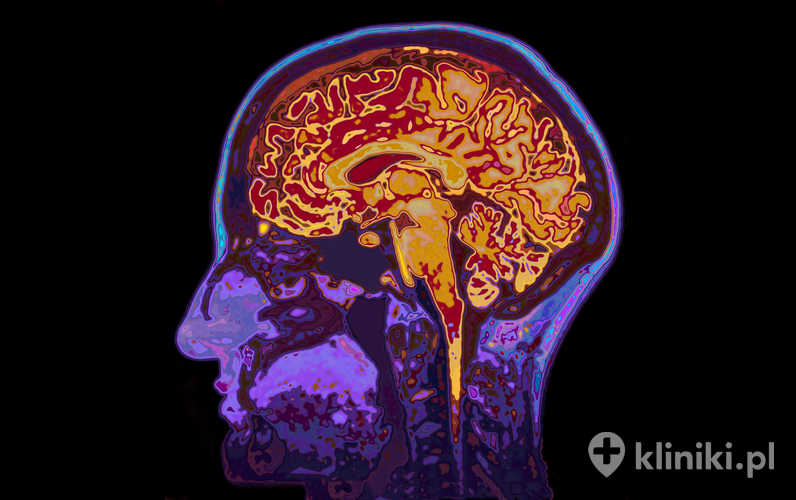

Badanie czynnościowe mózgu MR

Funkcjonalny magnetyczny rezonans jądrowy mózgu (fMRI – Funcional Mangetic Resonance Imaging)  jest nieinwazyjnym badaniem wykazującym się bardzo wysokim poziomem bezpieczeństwa, pozwalającym na zmierzenie aktywności mózgu. Łączy ze sobą elementy klasycznego badania rezonansem magnetycznym oraz elementy oceny przepływu krwi przez ten narząd.